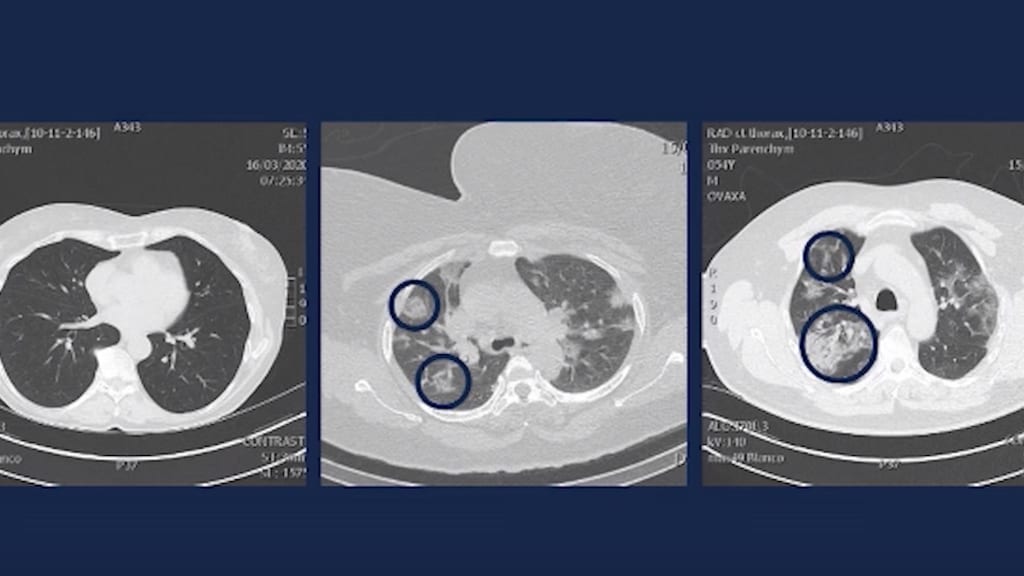

In de uitzending van Terzake laat de Vlaamse spoedarts ct-scans zien van longen, die eergisteren zijn gemaakt.

Op de linkerfoto zijn de longen te zien van een gezond iemand. "Op de middelste foto, in de twee blauwe cirkels, zijn longblaasjes die voor 20 tot 25 procent gevuld is met ontstekingsvocht."

Op de rechterfoto zie je longblaasjes die voor 80 tot 90 procent gevuld zijn met ontstekingsvocht, zegt Demeyer. "Dat is een massa die een litteken aan het vormen is."

Of zij nog kunnen genezen? "Uiteraard kunnen zij genezen, maar ze zitten in een levensbedreigende situatie. Dit zijn longen van sportieve, jonge mensen. Dit zijn geen rokers, geen mensen met suikerziekte, geen mensen met hartfalen."